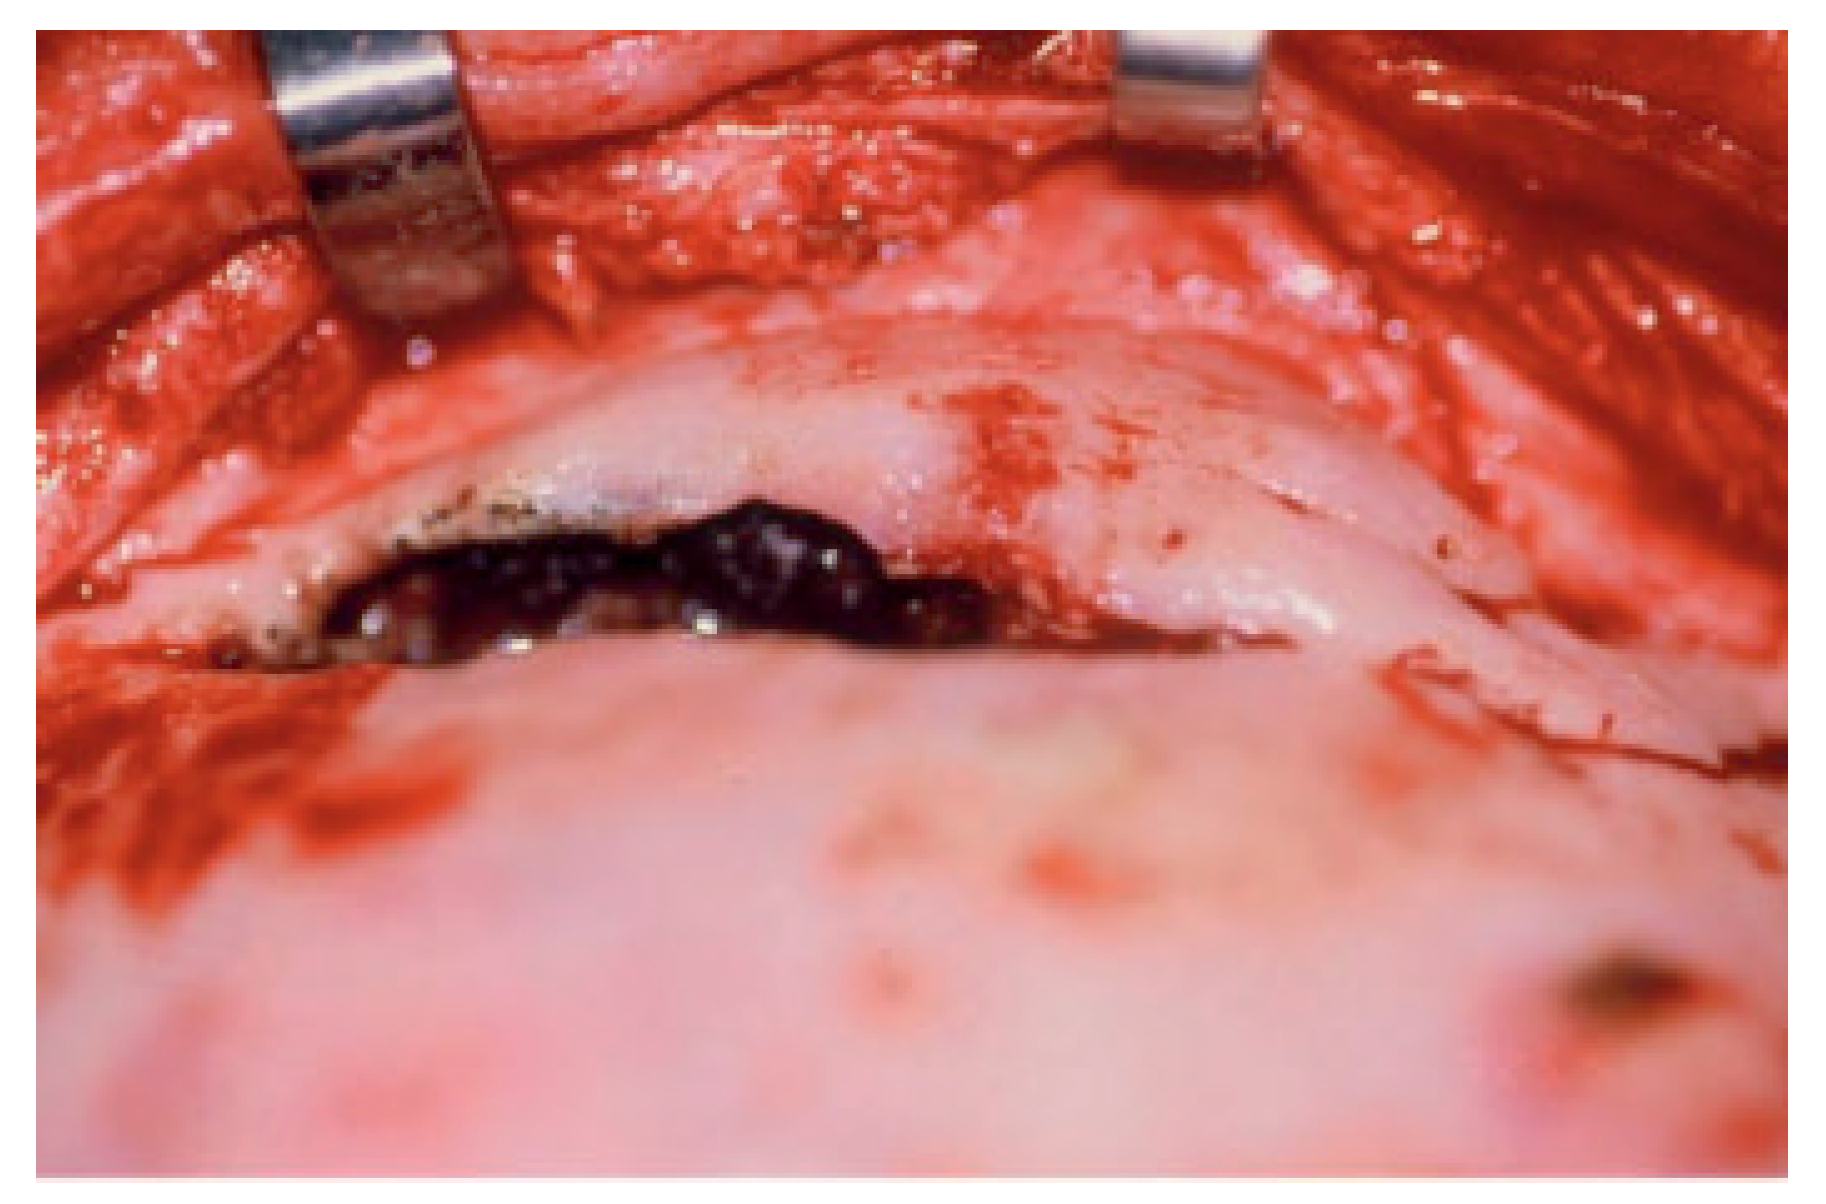

The most common skull-base complication encountered with frontal sinus fractures is mucocele (Figure 4). This is usually related to injury of the nasofrontal ostia (ducts) that is undiagnosed or poorly treated. The frontal sinus mucosa can be tenacious and if left behind after a frontal sinus fracture repair can manifest as a mucocele many years later (Figure 5) [18,19]. Mucopyocele is simply an infected mucocele and should be included in this category.

Figure 4.

Mucocele eroding through anterior table of old frontal sinus fracture patient. This particular case is 8 years after original treatment (reconstruction of anterior wall). This again demonstrates the need for constant follow-up and periodic imaging studies.

Figure 5.

The frontal sinus mucosa is tenacious. The mucosa looks black in this frontal sinus fracture with extension into the orbit. It is ciliated pseudostratified columnar epithelium with unidirectional sweeping motion toward the nasofrontal ostia. The mucosa is densely adherent to the diplopic veins via the foramina of Breschet.